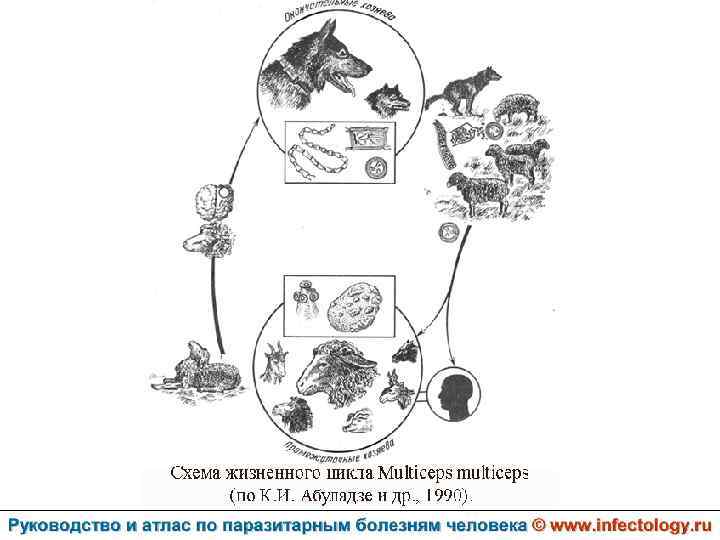

Ценуроз (шифр по МКБ 10 – B 71. 8)– спорадически встречающееся заболевание человека, вызываемое личиночной формой (ценуром) гельминтов рода Multiceps, половозрелые формы которых паразитируют у собак и диких волчьих. . Проявляется разнообразными клиническими симптомами в зависимости от вида паразита.